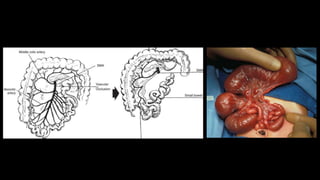

Má-rotação

• 1:500

• Volvo – isquemia

• 75% apresentação neonatal

• 10% após 1 ano de vida

• Clínica

• Vômitos biliosos

• Distensão abdominal

• Hemorragia gastrointestinal

• Associação com síndromes e outras desordens congênitas

• Atresia duodenal/jejunal

• Estenose

• Pâncreas anular

• Hirschsprung

• Intussuscepção

Embriologia

Má-rotação • 1:500 • Volvo– isquemia • 75% apresentação neonatal • 10% após 1 ano de vida • Clínica • Vômitos biliosos • Distensão abdominal • Hemorragia gastrointestinal • Associação com síndromes e outras desordens congênitas • Atresia duodenal/jejunal • Estenose • Pâncreas anular • Hirschsprung • Intussuscepção